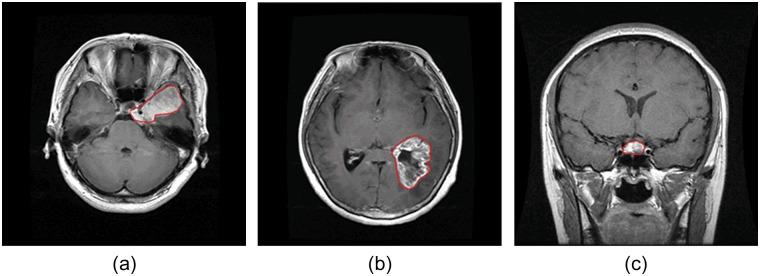

Automatic classification of tissue types of region of interest (ROI) plays an important role in computer-aided diagnosis. In the current study, we focus on the classification of three types of brain tumors (i.e., meningioma, glioma, and pituitary tumor) in T1-weighted contrast-enhanced MRI (CE-MRI) images. Spatial pyramid matching (SPM), which splits the image into increasingly fine rectangular subregions and computes histograms of local features from each subregion, exhibits excellent results for natural scene classification. However, this approach is not applicable for brain tumors, because of the great variations in tumor shape and size. In this paper, we propose a method to enhance the classification performance. First, the augmented tumor region via image dilation is used as the ROI instead of the original tumor region because tumor surrounding tissues can also offer important clues for tumor types. Second, the augmented tumor region is split into increasingly fine ring-form subregions. We evaluate the efficacy of the proposed method on a large dataset with three feature extraction methods, namely, intensity histogram, gray level co-occurrence matrix (GLCM), and bag-of-words (BoW) model. Compared with using tumor region as ROI, using augmented tumor region as ROI improves the accuracies to 82.31% from 71.39%, 84.75% from 78.18%, and 88.19% from 83.54% for intensity histogram, GLCM, and BoW model, respectively. In addition to region augmentation, ring-form partition can further improve the accuracies up to 87.54%, 89.72%, and 91.28%. These experimental results demonstrate that the proposed method is feasible and effective for the classification of brain tumors in T1-weighted CE-MRI.

感兴趣区域(ROI)的组织类型自动分类在计算机辅助诊断中起着重要作用。在当前研究中,我们专注于在T1加权对比增强磁共振成像(CE-MRI)图像中对三种脑肿瘤(即脑膜瘤、胶质瘤和垂体瘤)进行分类。空间金字塔匹配(SPM)将图像分割成越来越精细的矩形子区域,并计算每个子区域的局部特征直方图,在自然场景分类中表现出优异的结果。然而,由于肿瘤形状和大小的巨大差异,这种方法不适用于脑肿瘤。在本文中,我们提出了一种提高分类性能的方法。首先,通过图像膨胀得到的增强肿瘤区域被用作ROI,而不是原始肿瘤区域,因为肿瘤周围组织也可以为肿瘤类型提供重要线索。其次,将增强肿瘤区域分割成越来越精细的环形子区域。我们使用三种特征提取方法,即强度直方图、灰度共生矩阵(GLCM)和词袋(BoW)模型,在一个大型数据集上评估了所提方法的有效性。与使用肿瘤区域作为ROI相比,使用增强肿瘤区域作为ROI时,强度直方图、GLCM和BoW模型的准确率分别从71.39%提高到82.31%、从78.18%提高到84.75%、从83.54%提高到88.19%。除了区域增强之外,环形分割可以进一步将准确率提高到87.54%、89.72%和91.28%。这些实验结果表明,所提方法对于T1加权CE-MRI中的脑肿瘤分类是可行且有效的。